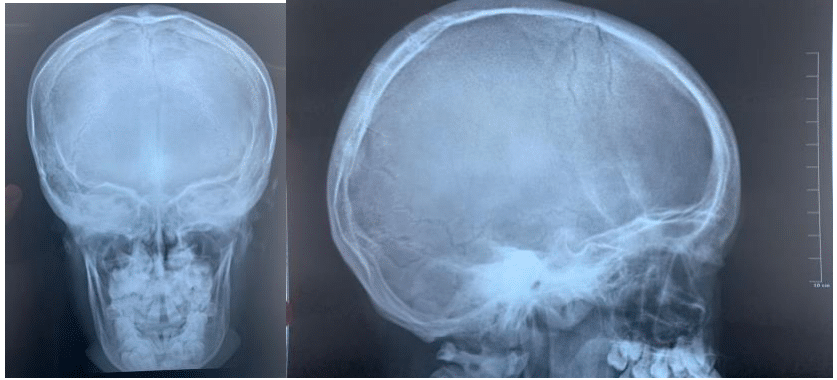

Radiographic studies including posteroanterior (PA) and lateral skull radiographs, PA chest radiograph, PA and lateral spine radiograph, and maxillary tomography were obtained (Figure 1).

Following radiographic evaluation, the characteristic cleidocranial dysostosis triad—supernumerary teeth, total or partial clavicular agenesis, and cranial alterations—was evident (Figure 2 & 3).

As per Tanaka et al.8 the diagnostic triad for cleidocranial dysostosis encompasses the complete or partial absence of clavicles, supernumerary teeth, and cranial anomalies including dysostosis of cranial sutures, failure of fontanelle closure, incomplete formation of the facial skeleton, and the absence of frontal and maxillary sinuses.